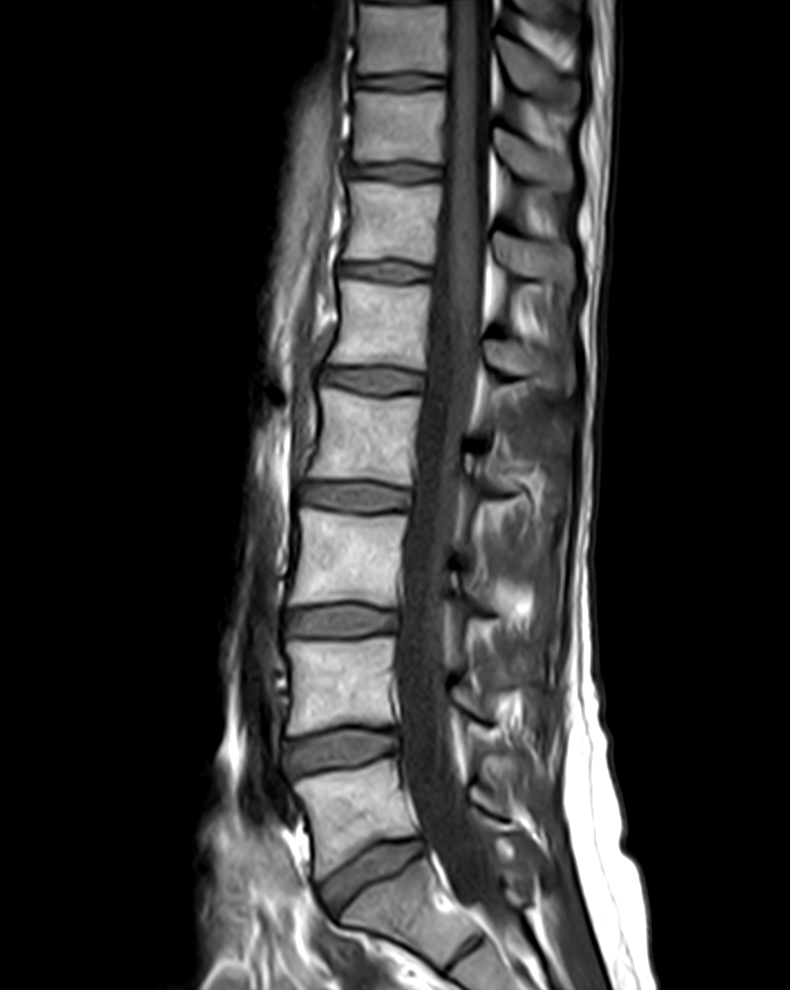

Sagittal T1w TSE